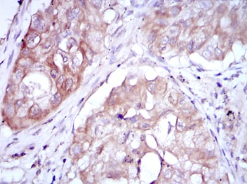

MTHFR Mouse Monoclonal antibody[5D3F3]

Species Reactivity:    Human,Rat

IHC    1/200 - 1/1000